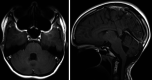

Observations: The authors present the case of a 14-year-old patient 8.2 years after CRT who experienced intracerebral hemorrhage. Autopsy demonstrated minimal pathological change without evidence of vascular malformation or aneurysm. These findings were unexpected given the degree of hemorrhage in this case. However, in the absence of other etiologies, it was believed that late-delayed radiation effect was the cause of this patient's fatal hemorrhage.